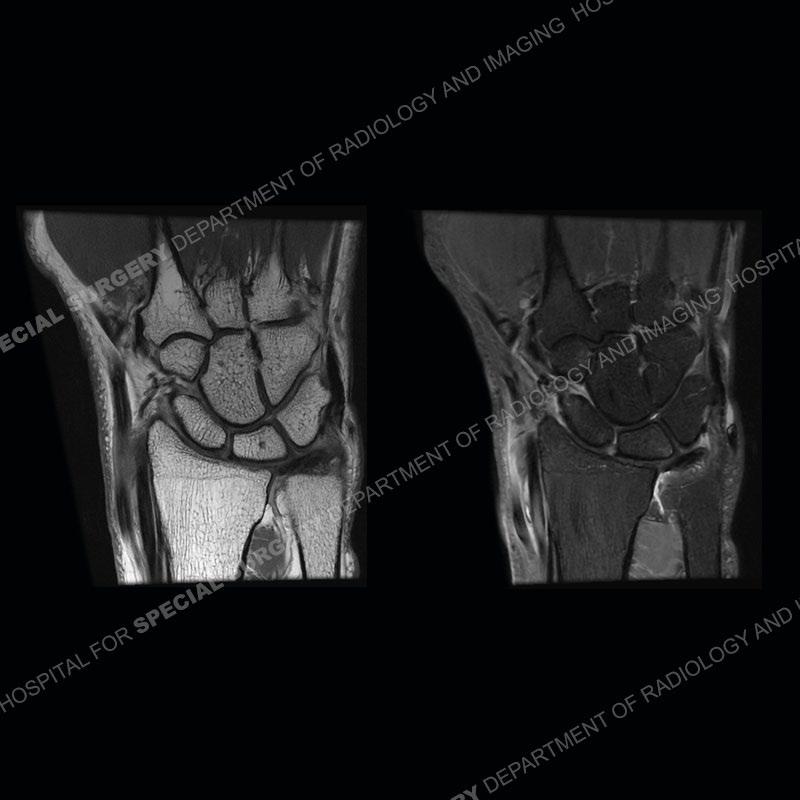

The radiographs in this case are not particularly contributory. The MRI demonstrates tenosynovitis of the first extensor compartment manifest by fluid/synovitis distention of the tendon sheaths. Multiple tendon slips are present of the abductor pollicis longus (APL) and with severe tendinosis seen of one of the tendon slips. Other areas of slightly increased signal and tendinosis are present of the components of the APL. Noted is a somewhat prominent septum separating the more dorsal extensor pollicis brevis (EPB) from the APL.

The first extensor compartment of the wrist contains the abductor pollicis longus or APL (slightly more volar) and the extensor pollicis brevis or EPB (slightly more dorsal). Tenosynovitis of this compartment is known by the eponym of DeQuervain’s tenosynovitis. In addition to tenosynovitis, tendinosis, and partial tearing can be seen. Complete disruption of the tendons is extremely uncommon. More common in women than men, this can affect almost any age patient. It is typically seen in individuals who perform repetitive gripping maneuvers or thumb overuse as can be seen in gripping a golf club or racket. The symptoms are frequently able to be managed with rest and ultrasound guided injections. Recalcitrant cases may require surgical intervention.

This case in particular highlights some of the normal variants of the first extensor compartment which can be confusing as well as clinically important. The APL can have multiple tendon slips with the insertion mostly being to the base of the thumb metacarpal but with additional insertions found of the trapezium and occasionally other thenar muscles. With additional tendinosis and partial tearing, this can become particularly confusing.

There can also be a partial or complete septum between the APL and EPB. This can particularly come into play with injections and positioning the needle into both sub-compartments to ensure that both tendons are bathed in the injectate.